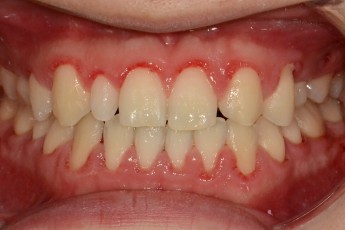

BEFORE & AFTER

- 돌출입교정